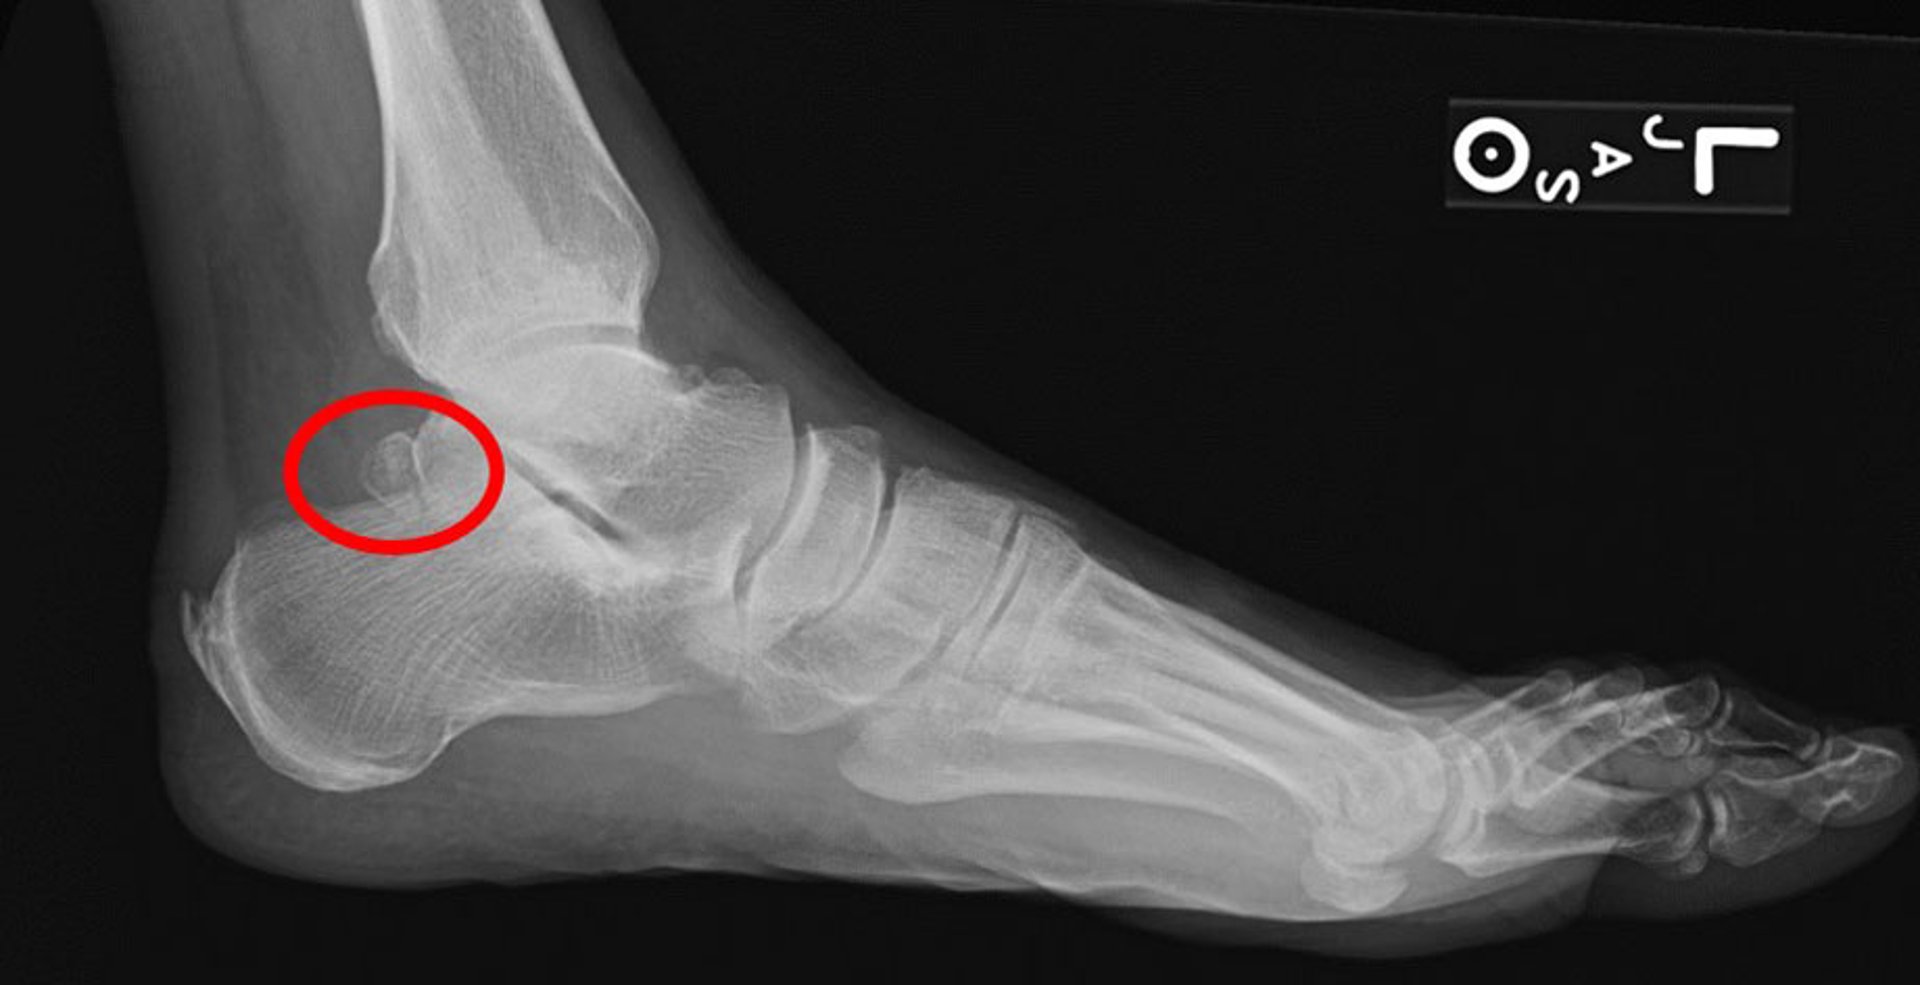

Os Trigonum

This lateral radiograph shows an os trigonum (circle).

Image courtesy of James C. Connors, DPM.